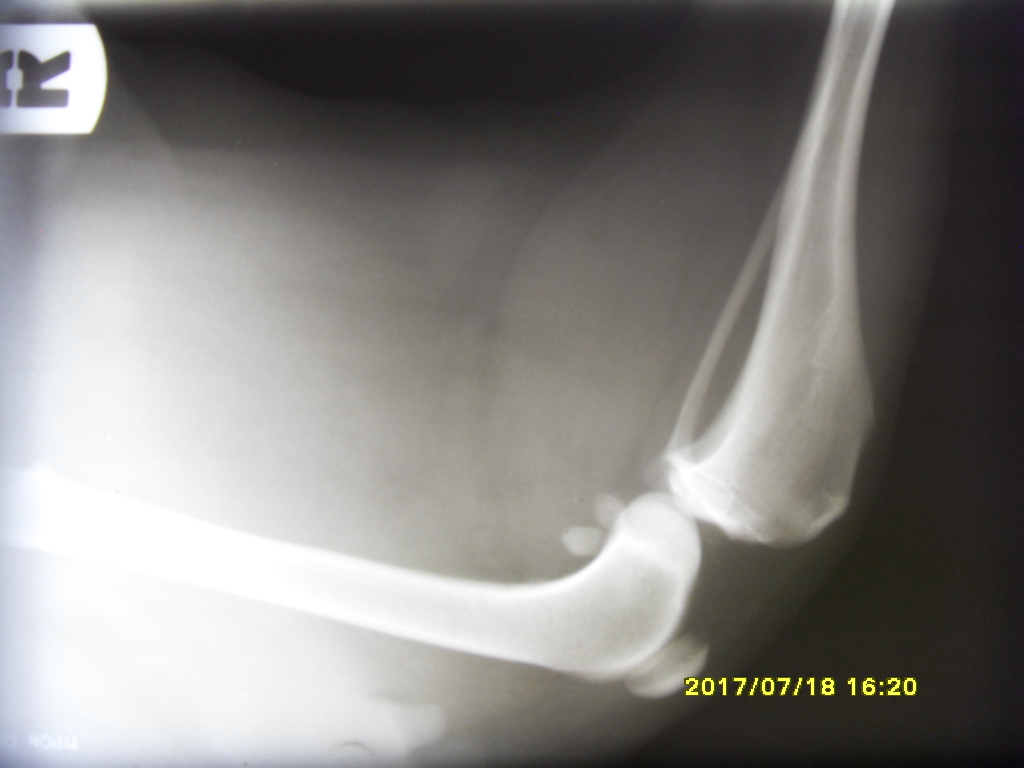

Keyq Posted July 18, 2017 Author Posted July 18, 2017 Cześc ponownie! Po dzisiejszej wizycie u weta i wykonanym teście szufladowym w premedykacji, lekarz stwierdził zerwanie więzadła krzyżowego lewej łapy. Zrobiono jej jeszcze RTG łapki i na zdjęciu było widać przesunięte kości i wysięk. Nela dostała zastrzyk z kwasem hialuronowym Synocrom Forte, Nasz psinka niestety nie może być operowana ponieważ Encorton który bierze osłabia układ odpornościowy, wystarczyło by kilka bakterii i infekcja albo inne komplikacje gotowe :/ Co do samych powiększonych węzłów chłonnych. Zrobiliśmy kolejne USG jamy brzusznej w pęcherzu moczowym dużo lepiej choć 2 "polipki" zostały jeszcze, badanie moczu wykazało ph 8, otoczka wokół nerki powiększyła się znacznie, śledziona dalej "marmurkowata". węzły szyjne zmniejszyły się o połowę (a myślałam że juz ich prawie nie ma:( ) pachwinowe znikły w całości. węzeł krezkowy nie zmniejszył się wcale :/. Powiem szczerze że spodziewałam się lepszych efektów. Encorton działa za słabo? co robić? Nie będę mogła zoperować psa póki Encorton nie wyleczy węzłów, wet jednak zalecił kolejna biopsje więc na następnej wizycie pobierze próbki z kilku węzłów, kolejne USG jamy brzusznej i krew. Lekarz kazał się jednak przygotować na najgorsze, Nela najprawdopodobniej ma chłoniaka. My z mężem już pogodziliśmy się z faktem że będziemy musieli się z nią pożegnać. :( poniżej wrzucam rtg zdrowej prawej i chorej lewej łapki Quote